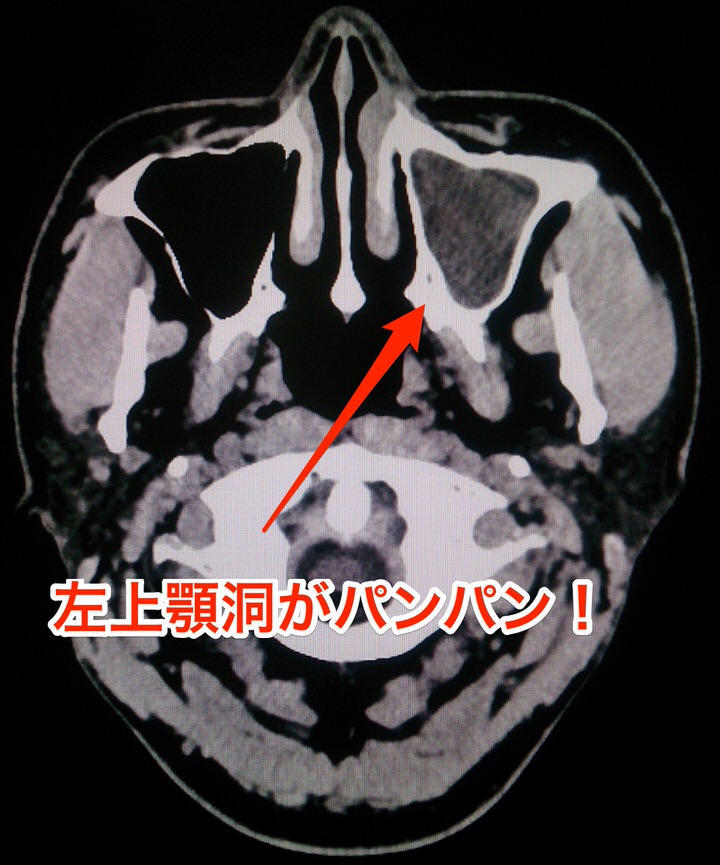

と思いつつ出勤。その日の夜は当直だったので、レントゲン技師さんにお願いしてCTを撮影。

左上顎洞の副鼻腔炎

「ああ、やっぱりなあ・・・」